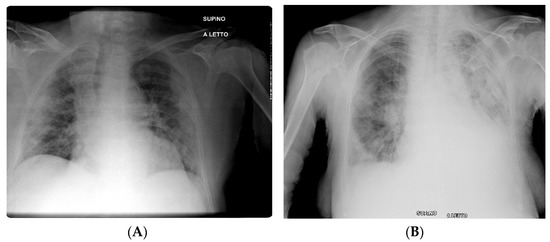

- Borghesi, A.; Maroldi, R. COVID-19 outbreak in Italy: Experimental chest X-ray scoring system for quantifying and monitoring disease progression. Radiol. Med. 2020, 125, 509–513. [Google Scholar] [CrossRef] [PubMed]

- Cozzi, D.; Albanesi, M.; Cavigli, E.; Moroni, C.; Bindi, A.; Luvarà, S.; Lucarini, S.; Busoni, S.; Mazzoni, L.N.; Miele, V. Chest X-ray in new Coronavirus Disease 2019 (COVID-19) infection: Findings and correlation with clinical outcome. Radiol. Med. 2020, 125, 730–737. [Google Scholar] [CrossRef] [PubMed]